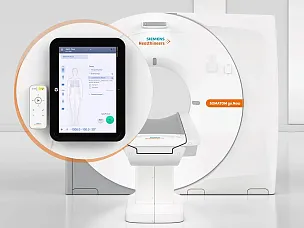

Siemens SOMATOM go.Up компьютерный томограф

SOMATOM go.Up - компьютерный томограф для проведения рутинных и целевых осмотров, лучевой терапии и ангиографии. Система отличается инновационным дизайном рабочего места и полностью обновлённой концепцией сервиса, которая способствует снижению расходов по эксплуатации. Подходит для обследования головного мозга, легких, толстой кишки, сердца, сосудов. Вы можете заказать или купить со склада в наличии компьютерный томограф Siemens SOMATOM go.Up по выгодной цене, от надежного официального дистрибьютора "МСТ", с бесплатной доставкой в любой город по всей России.

Система SOMATOM go.Up основана на новом мобильном рабочем процессе, в ней реализован ряд инновационных решений, которые обеспечивают высочайший уровень гибкости и мобильности в повседневных КТ-исследованиях. Эти решения также помогают повысить уровень комфорта для пациента и в перспективе обеспечат высокий уровень их удовлетворенности.

- Лёгкий планшет с высоким разрешением экрана дает полную свободу в организации работы

- Благодаря технологии Scan&GO для выполнения всего сканирования требуется лишь несколько шагов

- Вы можете проверить информацию о пациенте, как только пригласите его на исследование, и сразу же планировать сканирование на планшете, не отходя от пациента

- Вы все время находитесь рядом с пациентом, контролируя все процессы

- Простой в использовании пульт дистанционного управления с Bluetooth-каналом связи повышает мобильность рабочих процессов

- Пульт упрощает сканирование и повышает эффективность рабочего процесса

- Приложение для планшетных компьютеров, предназначенное для дистанционного управления сканированием

Guide&GO – инновационное решение на основе планшета, которое предназначено для проведения интервенционных процедур под контролем КТ. Оператор может выполнять процедуру с помощью планшета и пульта дистанционного управления, а для работы с изображениями использовать удобные функции сенсорного экрана, которые знакомы любому пользователю смартфона.